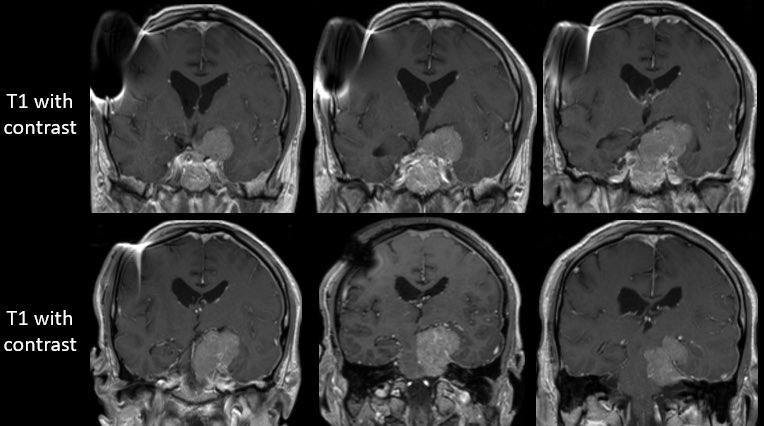

How would you manage this 42F w/ intracranial recurrence of optic nerve sheath meningioma initially biopsied at OSH 5 yrs ago. R eye blind, L 20/20, EOMI. Observation? Radiation? If surgery, approach/extent of resection? #Neurosurgery #MedEd #MedTwitter @EvaWuMD @TheJNS @WFNSHQ